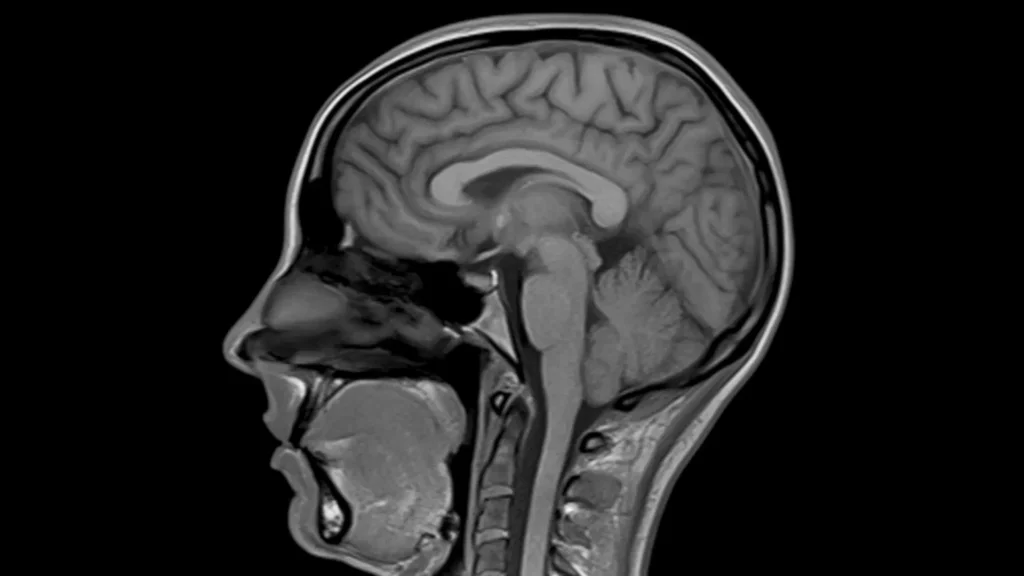

MRI

img01

Mri MAGNETOM Aera 1.5T Tesla

• Comfortable & Open

Wide 70 cm open design, quieter scans, and mostly feet-first exams to reduce anxiety and claustrophobia.

• Fast & Smooth Experience

AI-assisted technology for shorter scan time and higher resolution.

• Clear & Accurate Results

High-resolution images for brain, spine, joints, heart, abdomen, breast, and pediatric exams.

• Ideal for All Patients

Low table for easy access, supports up to 250 kg, and designed for children, elderly, and nervous patients.

• Safe With Implants & Movement

Advanced motion and metal-artifact reduction for clean images even if you move or have implants.

• Eco-Friendly & Reliable

Zero helium boil-off for safer, eco-conscious performance.

• Exceptional image quality

With Tim 4G Technology